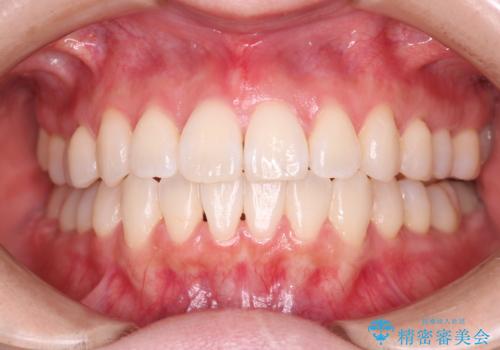

[マウスピース矯正] がたがたの歯並びをきれいにしたい

![[マウスピース矯正] がたがたの歯並びをきれいにしたいの症例 治療前](https://seimitsushinbi.jp/wp/wp-content/uploads/2025/06/0d238550c8a0fddc4de7b2c337c6c786-500x350.jpg?v=1750323380)

![[マウスピース矯正] がたがたの歯並びをきれいにしたいの症例 治療後](https://seimitsushinbi.jp/wp/wp-content/uploads/2025/06/IMG_0002-2-500x350.jpg?v=1750323305)